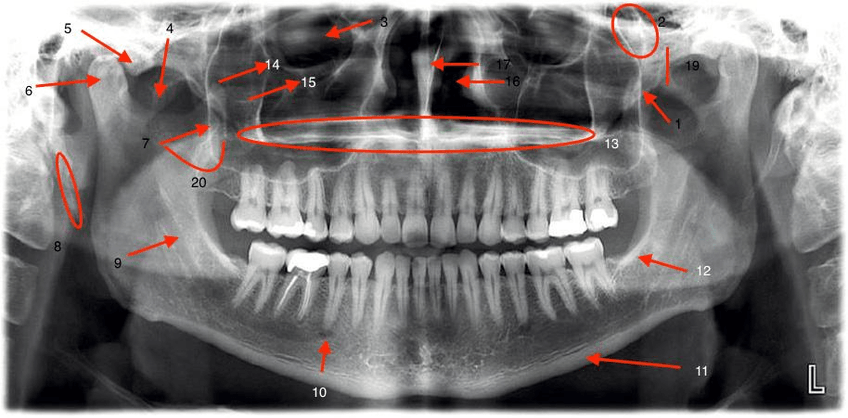

IMÁGENES

He publicado nuevos apuntes de 2º Radiología bucal: IMÁGENES

Con-letra.jpg

Sin-letra.jpg